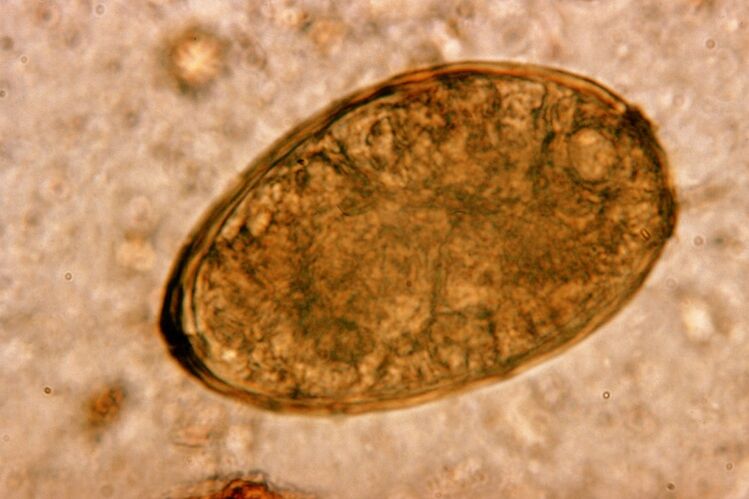

These flukes live in pairs in the lungs, forming cysts in the bronchi.Infestation occurs when eating crabs and crayfish infected with parasites.Once in the gastrointestinal tract, pulmonary fluke penetrates the peritoneum and reaches the lungs through the diaphragm, causing the patient to cough continuously.

Lungworms are small worms, which belong to the class of trematodes, “specialize” in parasitizing especially in the lungs.For example, this disease causes more serious problems with the respiratory system than roundworms.

At the site of its localization, an infiltrate appears and hemorrhage develops, as a result of which a cavity appears filled with rotting worm metabolites, dead parasites and lung tissue.The danger caused by lungworm disease is further exacerbated by the fact that the disease is long-lived and can live in the host's body for up to 20 years.